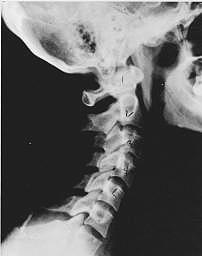

Near Normal

Subluxation Degeneration - Normal This is a side x-ray view of the neck. As with all the pictures you will see on this page, the patient is looking to the right of the screen, so you are viewing the right side of their neck. We will call this picture a "near normal" spine. Compare this spine with the ones you will see below on this page. Notice the normal forward curve of the neck. This curve helps absorb shock. Notice how each of the disc spaces between C2 (second bone in neck) and C7 are thick and even, this again is normal. Also notice how the front portions (right on the x-ray) of each of the vertebrae (called the 'body' of the vertebrae) are fairly square with clear and well defined borders. This type of arrangement is normal in the neck. Normal vertebrae in other parts of the spine also have similar characteristics to what we see here. When subluxations occur and are left uncorrected, ongoing relentless changes occur that result in damage to the structure and function of the spine along with nerve damage and the resulting problems caused from improper nerve supply.